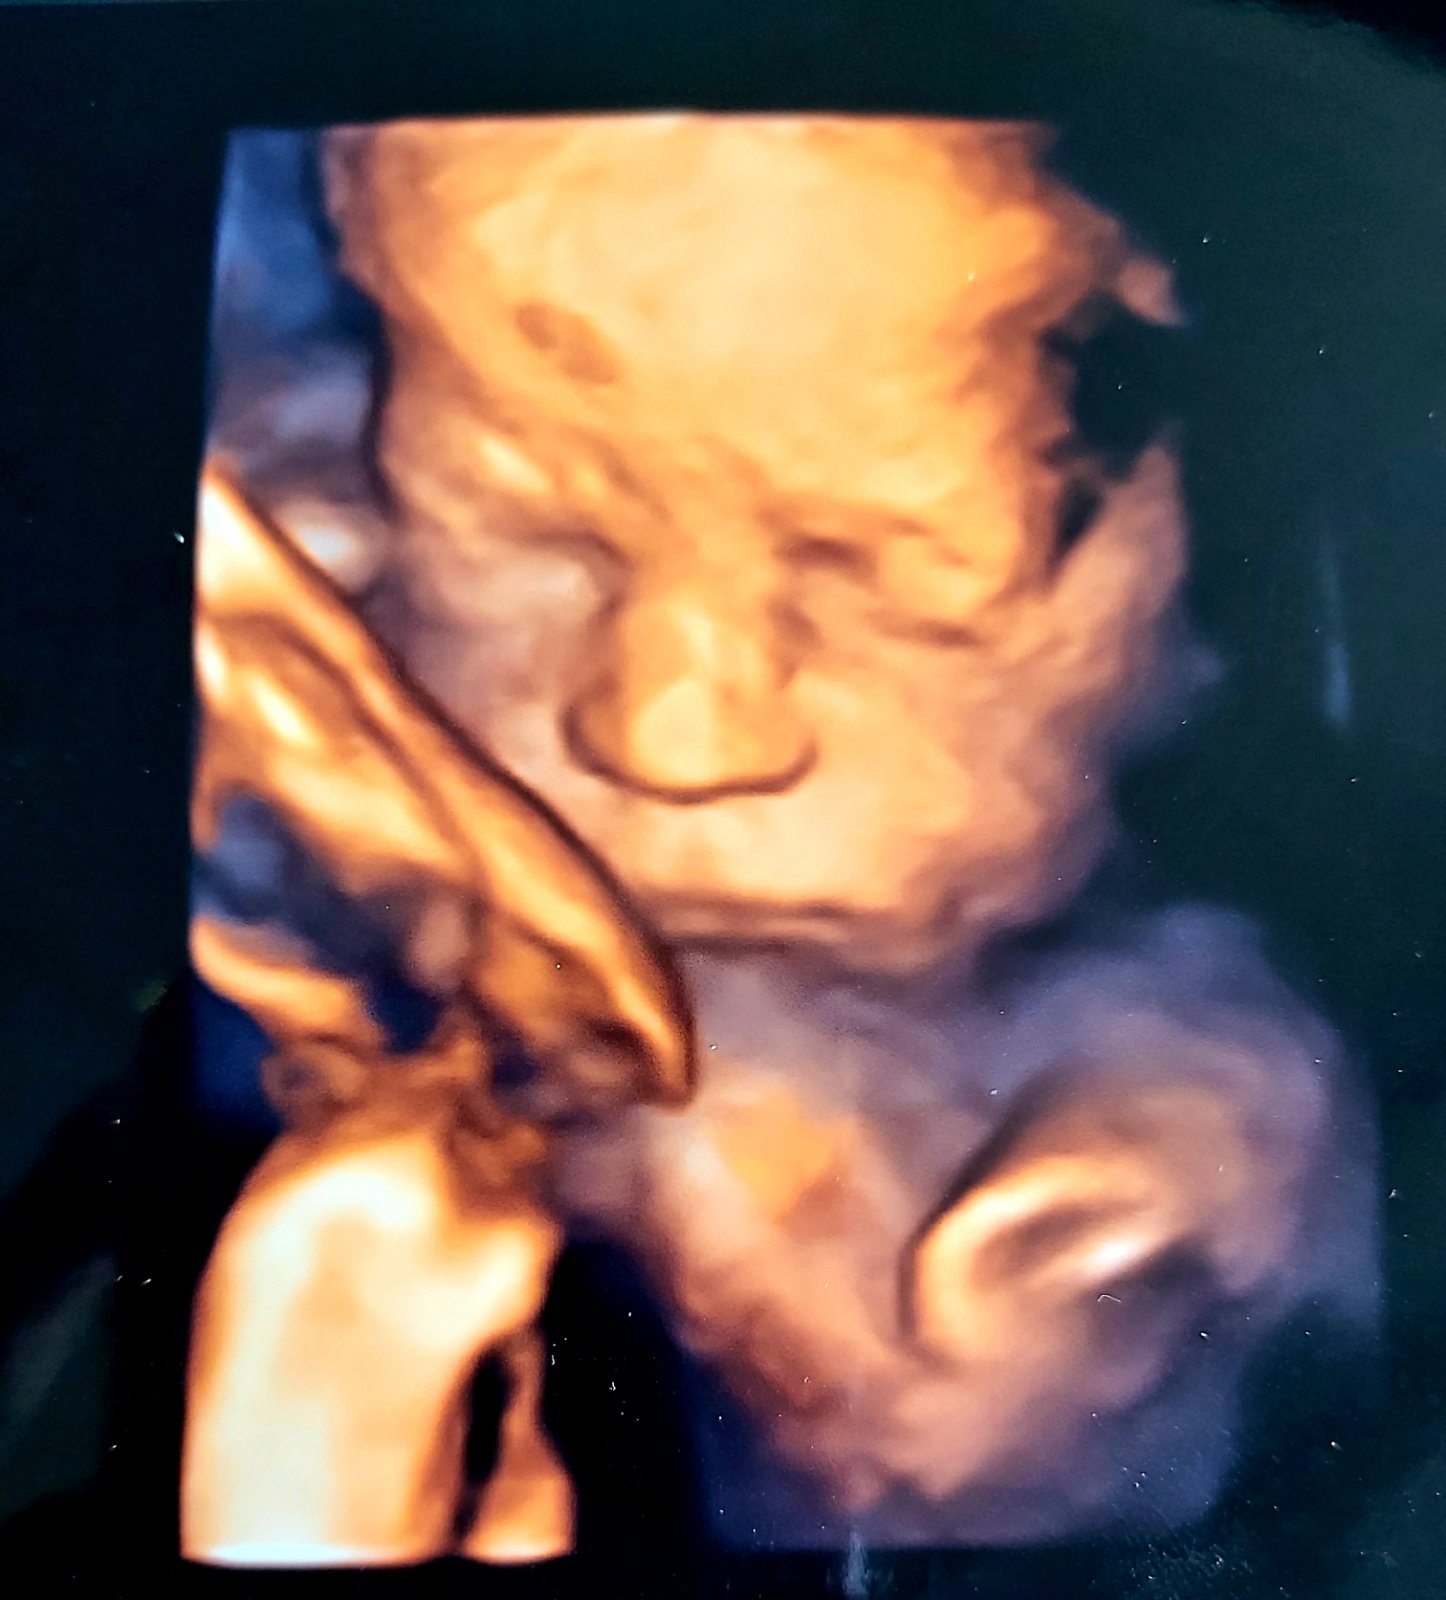

28tt+3 1309g,stale hlavickou hore😏